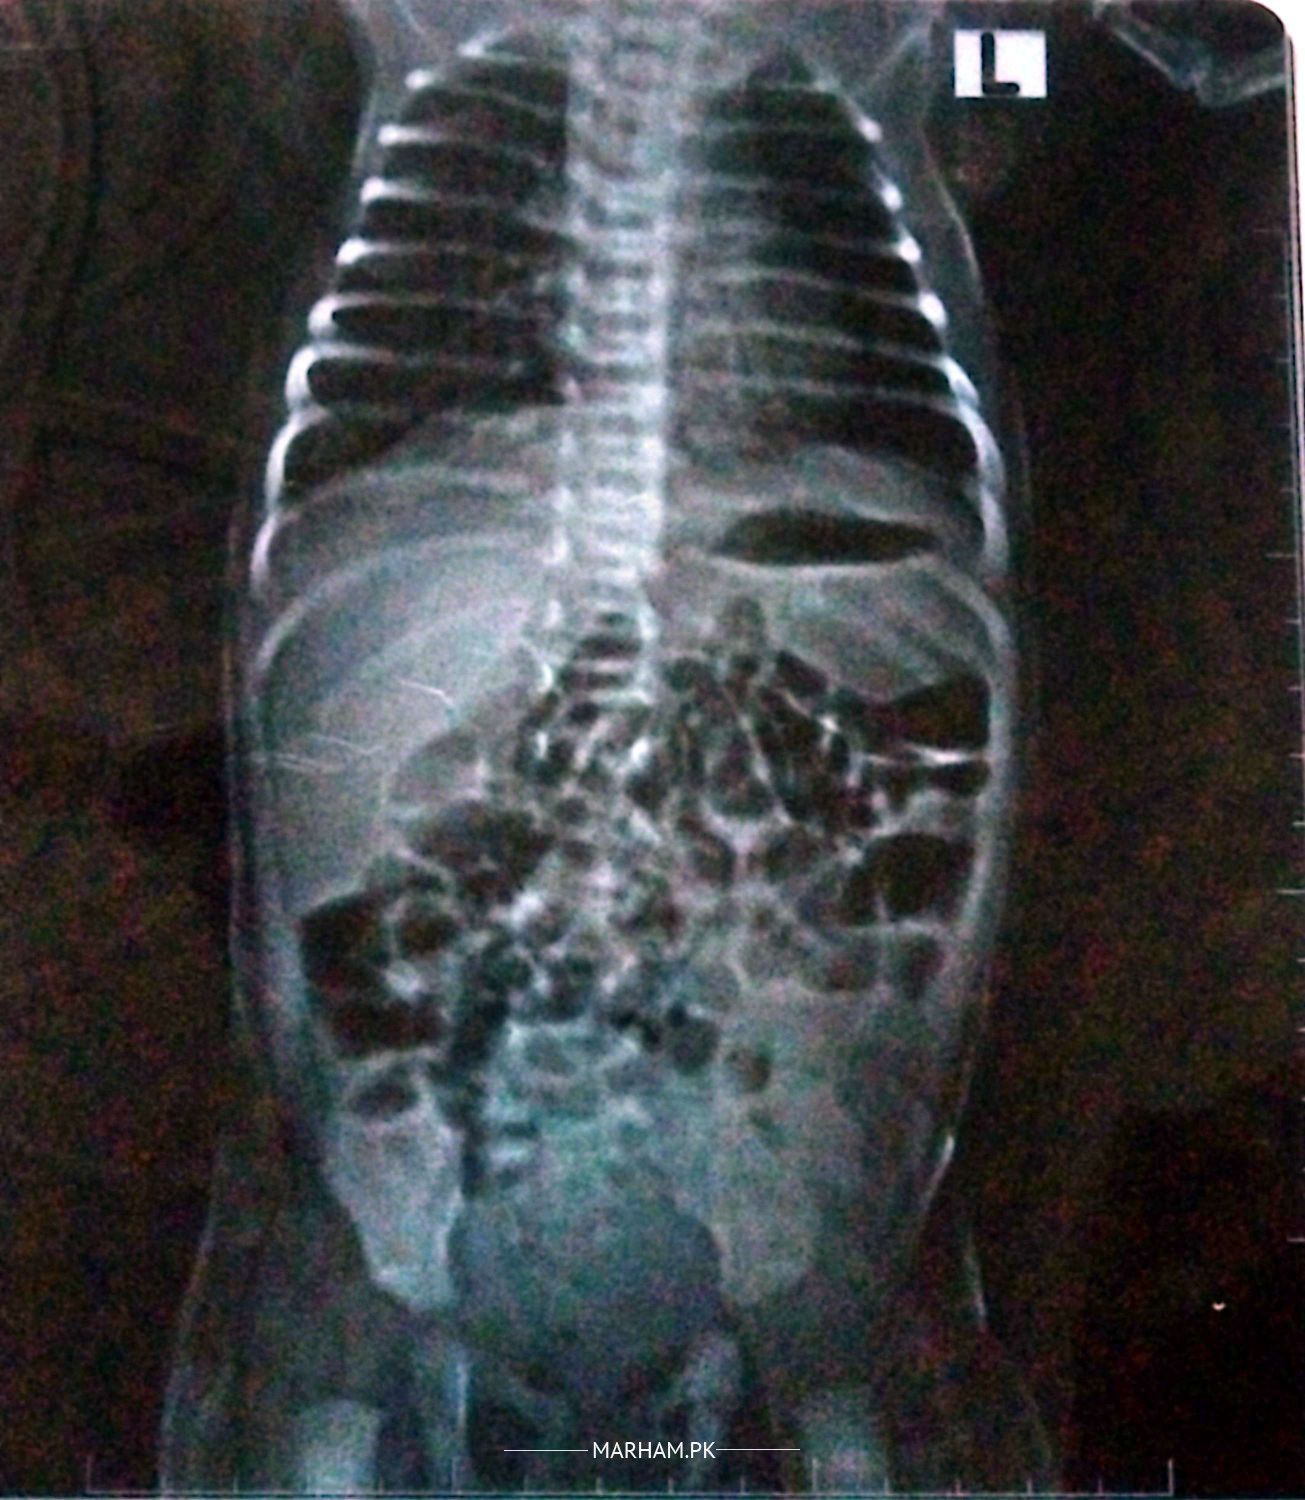

My daughter is one month old. She passed meconium at the time of delivery; however, since then, she has not been able to pass stool on her own. She only passes stool when a glycerin suppository is inserted; otherwise, she does not. We have consulted a doctor, who advised an X-ray, and an ultrasound was also performed. According to the ultrasound report, everything appears normal. Despite this, I am concerned about why she is unable to pass stool independently. Kindly guide me on what steps I should take?

kindly see a paediatrician and paediatric surgeon for a full assessment. there seems to be gaseous distention with decreased air in rectum/pelvic region. also don't make a habit of giving suppositories, motherfeed two hourly

we have consulted a pediatrician.he has prescribed ezigut drops,dromax,skilax drops.it has been 5 days that i am giving her these medicines but still she is not passing stool by her own.i have attached ultrasound report alongwith my post